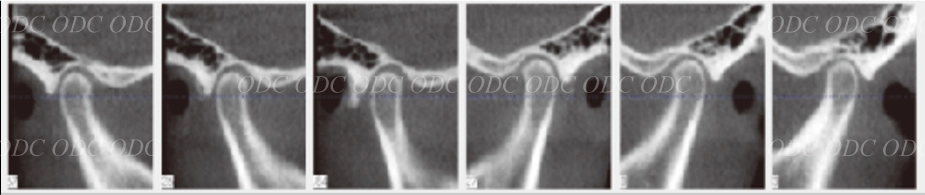

円板後部結合組織は繊維化を示し、偽円板化を示している。右側で顕著である。

両側下顎頭に骨髄信号の異常は認められない。両側関節円板は前方転位をしている。

初診時に患者が訴えていた顎関節部の痛みはこれによるものと思われる。

両側上下関節腔に貯留が認められ、特に右側で顕著である。

両側関節円板は前方転位をしている。後部結合組織は両側共にさらに偽円板化が亢進したことが分かる。両側上下関節腔に認められていた液貯留がほぼ消失した。

定期的にMRIを撮影し、顎関節の状態を把握しながら治療を進めてきたので、咬合再構成による顎関節への大きなダメージを与えることなく治療を完了することが出来たと考察した。